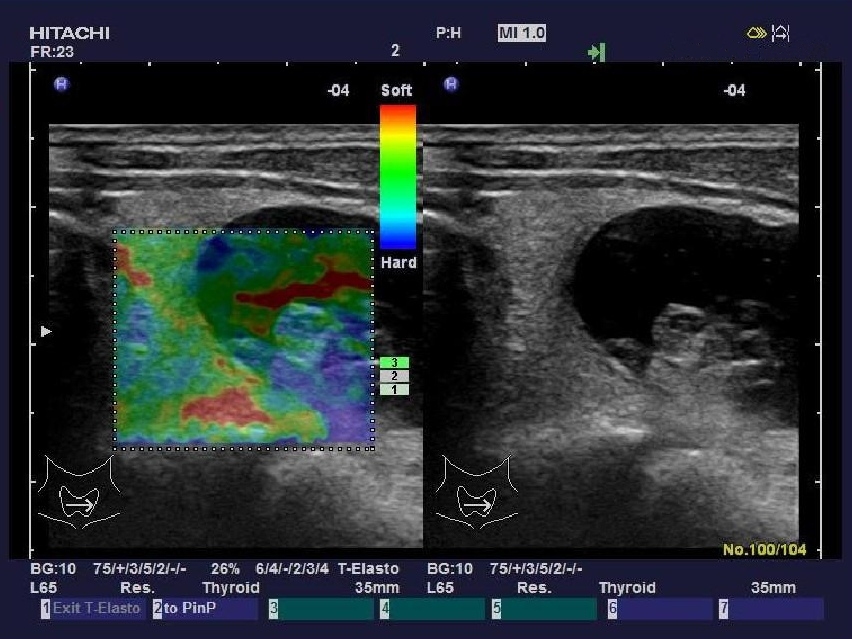

實時組織彈性成像技術(shù)

(Real-time Tissue Elastography)

“ARIETTA 70”加載了彈性成像功能,實時組織彈性成像技術(shù)是根據(jù)人體不同組織受壓后的變形差別,將其不同的組織的彈 性系數(shù)差異用不同的彩色顯示出來的新成像診斷技術(shù)。

組織彈性成像技術(shù)完全脫離了常規(guī)超聲聲阻抗成像原理,開辟了超聲診斷原理的新領(lǐng)域。將指尖的觸診高速信息化數(shù)字化,不 僅實現(xiàn)了定性分析,還具備定量分析功能。

臨床應(yīng)用領(lǐng)域:乳腺、甲狀腺、前列腺、皮膚、肝臟、子宮、卵巢、胰 腺、淋巴結(jié)、血管、直腸、睪丸、顱腦及多種術(shù)中檢查。